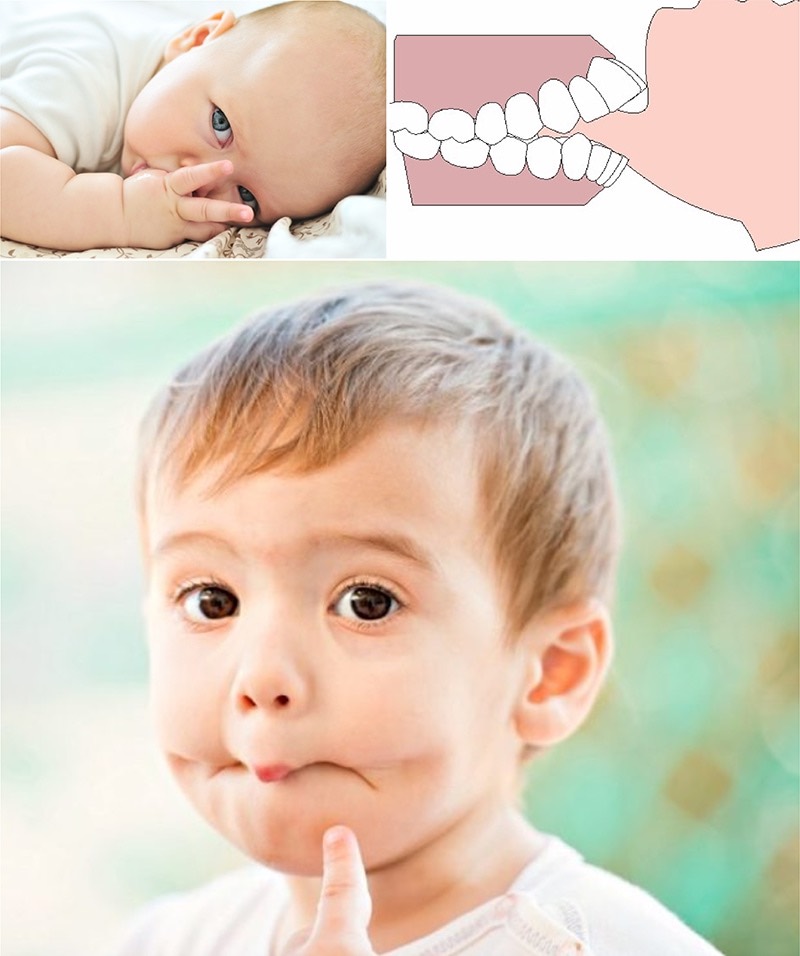

簡單來說,肌功能異常就是患者有口腔的習癖,如咬指甲、吸大拇指、咬下唇等,這些看似不經意的小習慣,長期下來對牙齒及臉型都有巨大的影響。當牙弓空間不足,就容易造成往前的推擠力量,而最後表現出來比較容易看到的就是前牙暴牙。